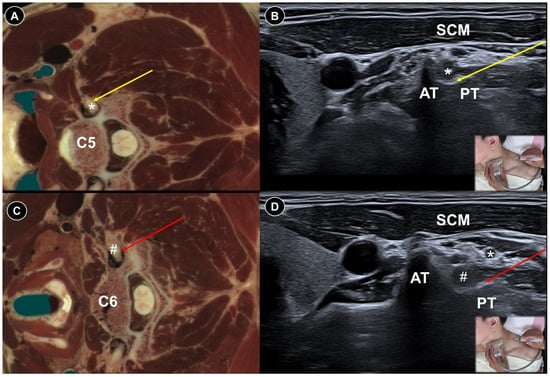

- Cui, X.; Zhang, D.; Zhao, Y.; Song, Y.; He, L.; Zhang, J. An open-label non-inferiority randomized trail comparing the effectiveness and safety of ultrasound-guided selective cervical nerve root block and fluoroscopy-guided cervical transforaminal epidural block for cervical radiculopathy. Ann. Med. 2022, 54, 2669–2679. [Google Scholar] [CrossRef]

- Joo, H.J.; Choi, S.; Kim, B.H.; Kim, M.-S.; Shim, G.Y.; Chung, S.J.; Chon, J.; Yoo, M.C.; Soh, Y. Therapeutic Efficacy of Ultrasound-Guided Selective Nerve Block on Chronic Cervical Radiculopathy. Medicina 2024, 60, 1002. [Google Scholar] [CrossRef]

- Lee, S.H.; Choi, H.H.; Roh, E.Y.; Chang, M.C. Effectiveness of ultrasound-guided pulsed radiofrequency treatment in patients with refractory chronic cervical radicular pain. Pain Physician 2020, 23, E265. [Google Scholar] [CrossRef]

| Acute herpes pain | Burning, stabbing, or itching pain in the affected dermatomal distribution | Reactivation of VZV leading to viral nerve damage and inflammation | Cervical: supine, head turned to contralateral side Thoracic: prone | Cervical:

| Painful radiculopathy | Pain, numbness, clumsiness and even weakness in the distribution of the affected nerve root | Mechanical compression and inflammatory irritation of the nerve root, often due to disc herniation or spondylosis | Cervical: supine, head turned to contralateral side Lumbar: prone | Cervical: linear, in-plane

| Improvement of pain by ESI (meta-analysis), SNRB/caudal block (RCT) |